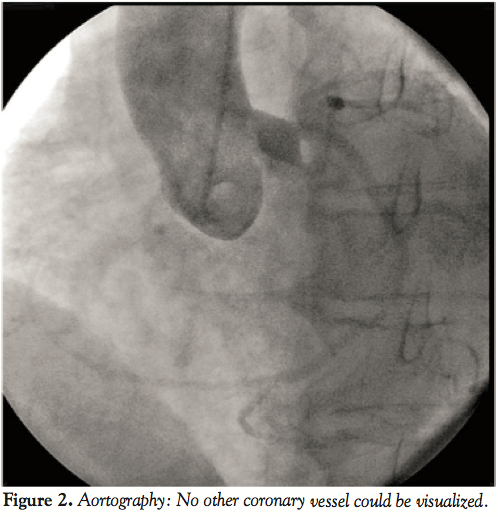

Coronary angiography performed via a right radial artery approach

revealed a single coronary artery (SCA) originating from the left sinus of Valsalva (L-I type) (Figure 1). No other coronary artery was noted on aortography (Figure 2). The left main was very short; the LAD and circumflex had separate ostia. The LAD had a paraostial subtotal occlusion and another focal 80% stenosis at its mid segment (Figures 3 and 4). A superdominant circumflex artery, after supplying the posterior descending branch, continued its course along the right posterior atrioventricular groove providing branches for the right ventricle and right atrium.